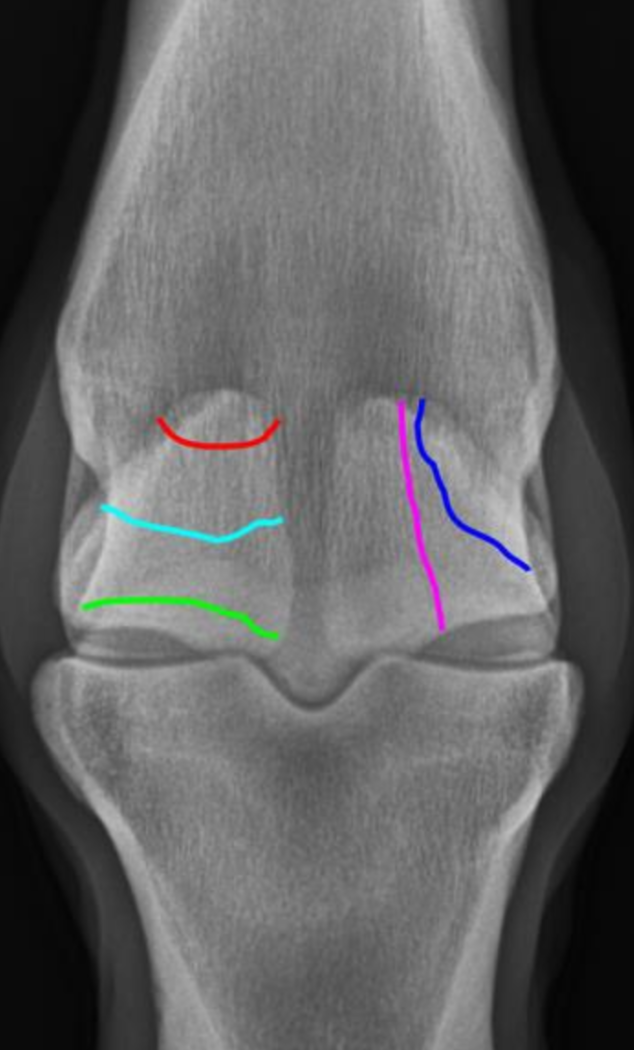

which OCD lesions are these in the dog

A = cd humerus

B = medial humeral condyle (elbow)

C = medial trochlear ridge (ankle)

D =lateral femoral condyle (knee)